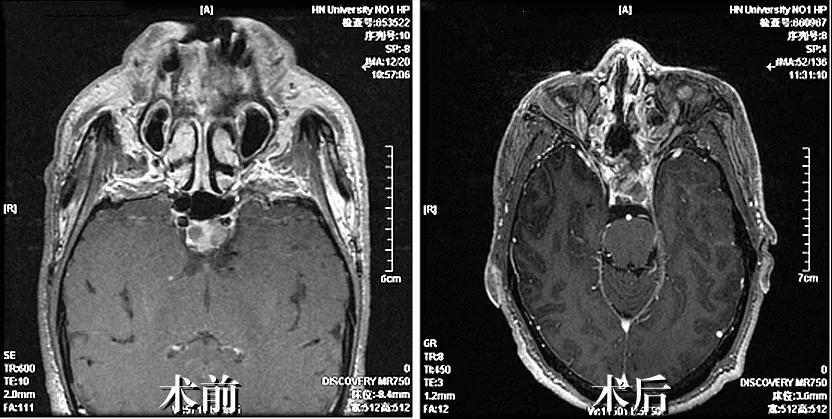

患者赵先生,56岁,因心肌炎、心力衰竭在当地医院住院治疗检查时发现鞍区占位,待症状好转后为求进一步治疗鞍区占位病变来到我院神经外科就诊。主治医师王晓斌接诊后,查体发现患者存在口唇肥厚、四肢关节增大明显等症状,为患者行内分泌激素化验回示生长激素偏高,垂体MRI检查回示考虑垂体腺瘤可能大。科室副主任马建功组织科室人员进行病情讨论,考虑患者生长激素腺瘤导致患者心肌肥厚、心力衰竭,患者在住院期间一度出现重度心力衰竭,请心血管内科专家会诊,给予纠正心功能冶疗。待患者心力衰竭纠正并稳定后,邀请麻醉与围术期医学科专家为患者进行术前评估,在充分的术前准备后,马建功团队为患者实施了“神经内镜下经鼻蝶入路鞍区占位切除术+颅底重建术”。手术历时五个多小时,完整切除肿瘤,术后病理结果回示垂体腺瘤(生长激素型),术后复查生长激素恢复正常。患者现已康复出院,未出现神经功能障碍。